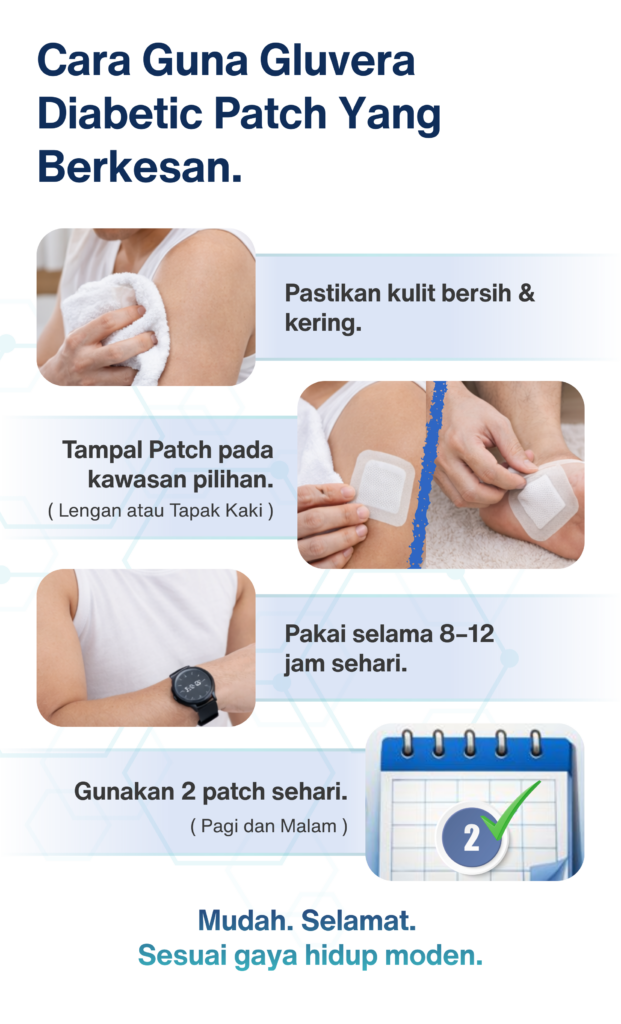

Adakah penggunaan GLUVERA™ menyakitkan?

Tidak. Patch ini tidak menyakitkan, nipis dan selesa dipakai semasa aktiviti harian.

Adakah GLUVERA™ menyebabkan rasa panas atau pedih pada kulit?

Kebiasaannya tidak. Namun, hentikan penggunaan jika berlaku iritasi dan rujuk profesional kesihatan.

Perlukah GLUVERA™ digunakan setiap hari?

Untuk sokongan yang konsisten, GLUVERA disarankan digunakan sekali sehari mengikut keperluan individu.

Bolehkah GLUVERA™ digunakan ketika berpuasa atau sibuk bekerja?

Ya. GLUVERA tidak bergantung kepada waktu makan, sesuai untuk rutin harian dan gaya hidup aktif.